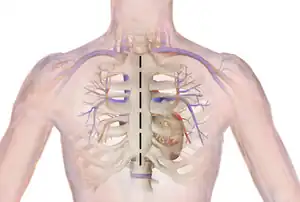

Ross Procedure

Ross procedure, also known as pulmonary autograft, is a type of aortic valve replacement to treat severe aortic valve disease, usually in children and young adults with a bicuspid aortic valve.[2] It involves removing the diseased aortic valve, situated at the exit of the left side of the heart (where the aorta begins), and replacing it with the person's own healthy pulmonary valve (autograft), removed from the exit of the heart's right side (where the pulmonary artery begins).[3] To reconstruct the right sided exit, a pulmonary valve from a cadaver (homograft), or a stentless xenograft, is used to replace the removed pulmonary valve.[2][lower-alpha 1] Compared to a mechanical valve replacement, it avoids the requirement for thinning the blood, has favourable blood flow dynamics, allows growth of the valve with growth of the child and has less risk of endocarditis.[2]

Several adaptations of the Ross procedure have evolved, but the principle is essentially the same; to replace a diseased aortic valve with the person's own pulmonary valve (autograft), and replace the person's own pulmonary valve with a pulmonary valve from a cadaver (homograft) or a stentless xenograft.[2][3] It is an alternative to a mechanical valve replacement, particularly in children and young adults.[7] It avoids the need for thinning the blood, has favourable blood flow dynamics and the valve grows as the person grows.[7]

Before the operation, preparations include transthoracic echocardiography and measurements of the ascending aorta and the pulmonary valve.[10] Under general anaesthesia, the chest is cut open in the midline.[5] The heart and aorta are exposed before the heart is temporarily stopped and its function taken over cardiopulmonary bypass.[5] Subsequent steps include removing the diseased aortic valve and mobilizing the coronary arteries, followed by harvesting and preparing the person's own healthy pulmonary valve, before implanting it within the left ventricular outflow tract, the exit of the left side of the heart (where the aorta begins).[2][10] Then the coronary artery is reimplanted, before the pulmonary homograft is implanted in the right ventricular outflow tract, the exit of the heart's right side (where the pulmonary artery begins).[2][10] The pulmonary autograft is joined with the ascending aorta.[2][10]